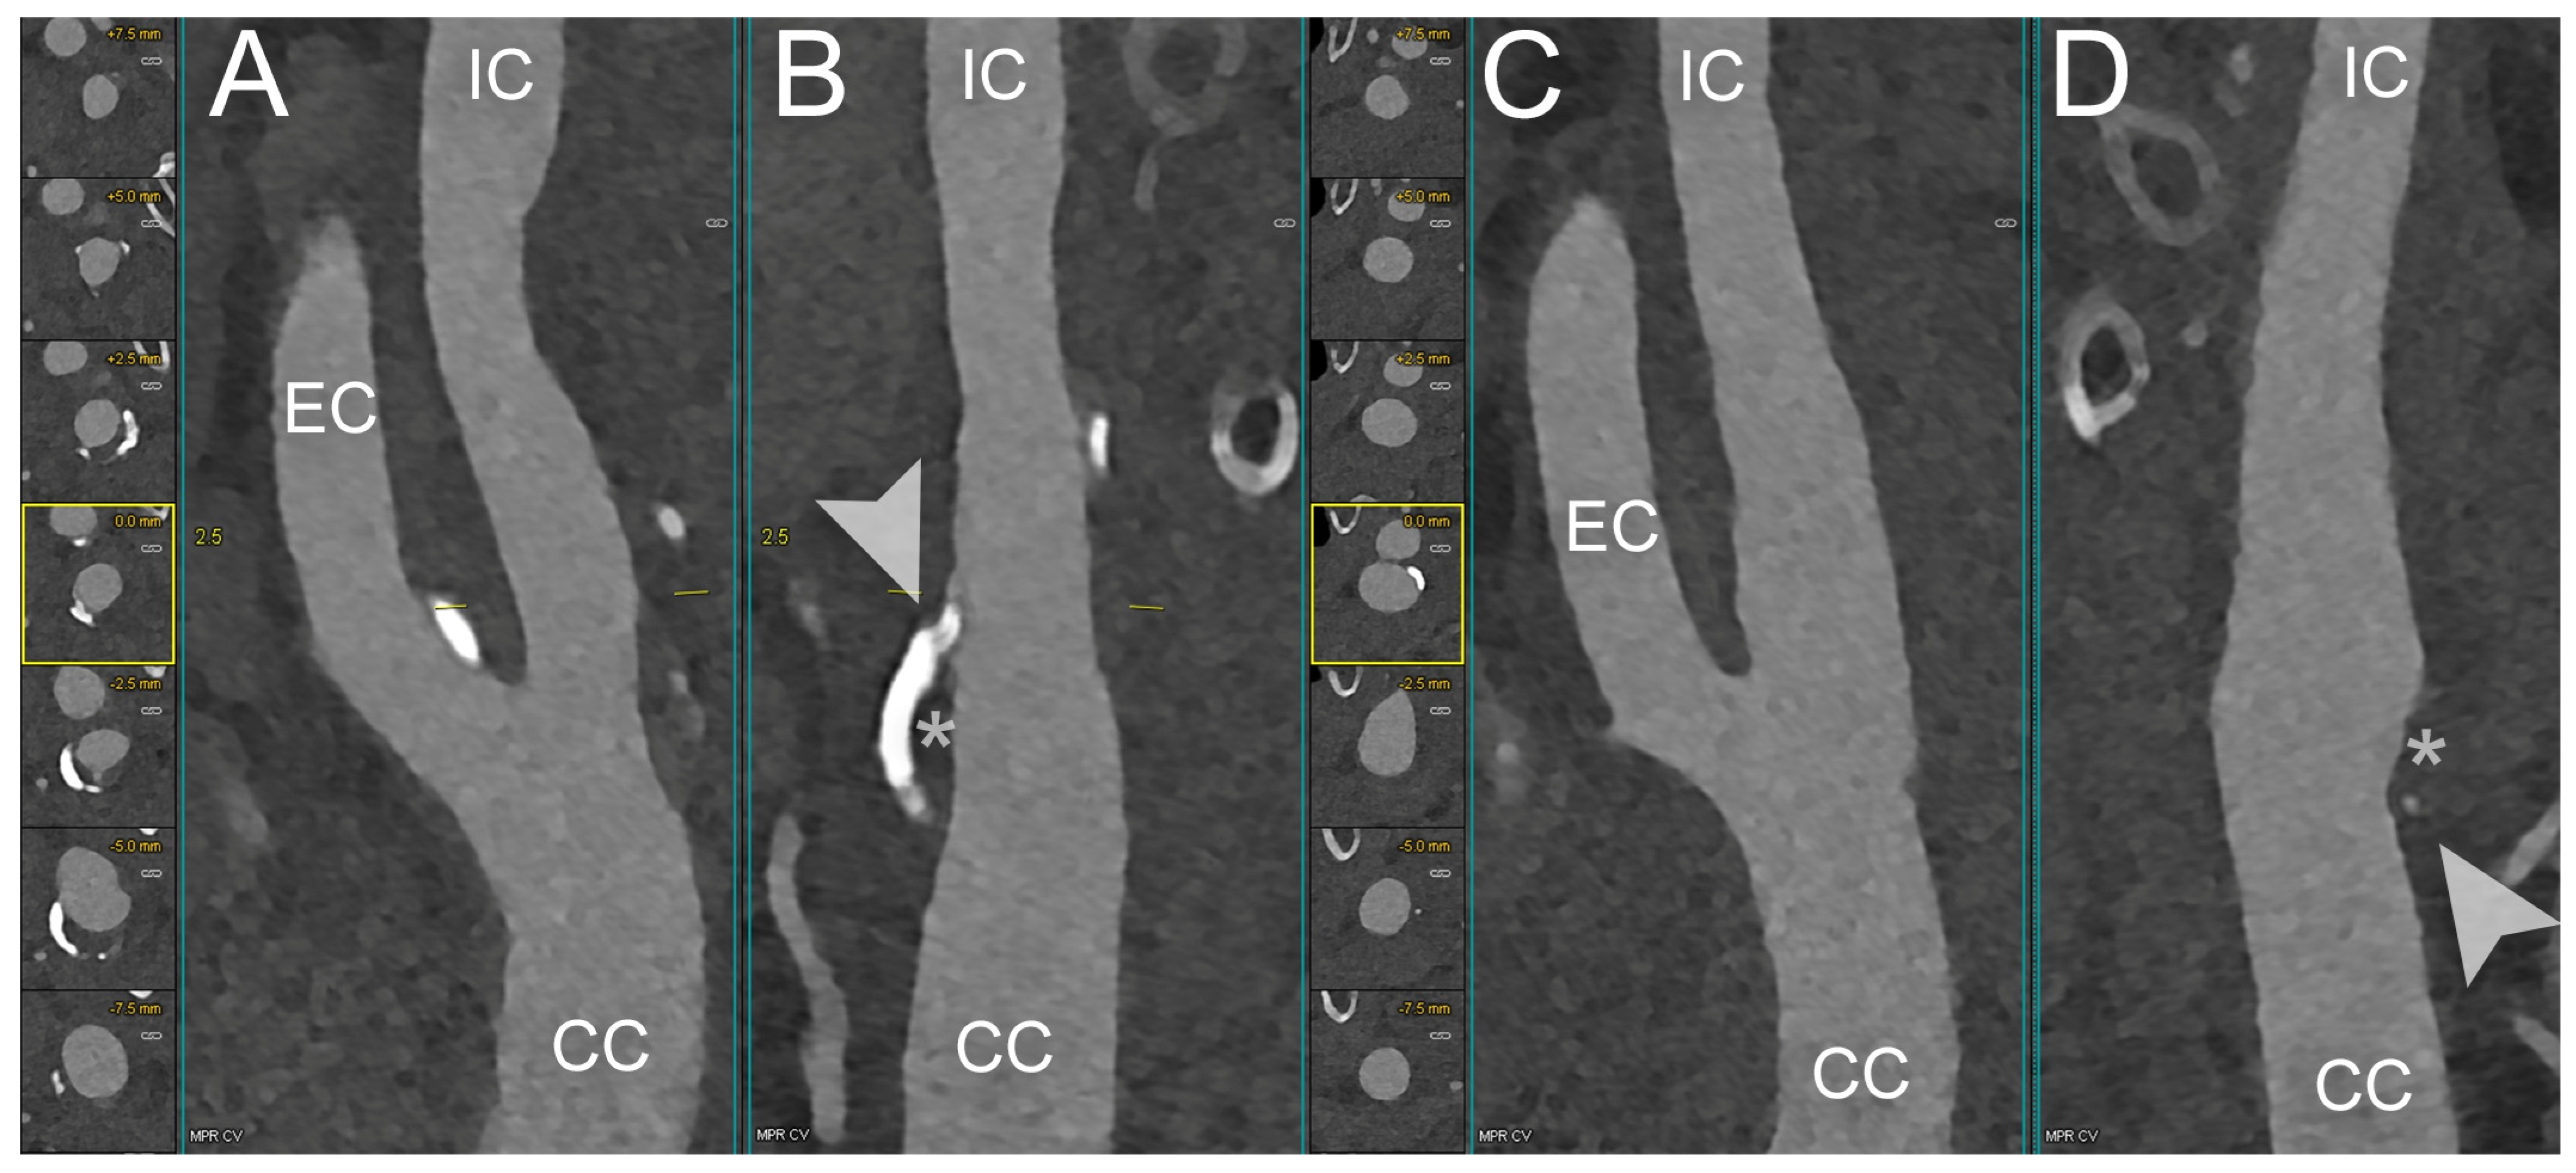

4. Clinical Application of PCCT in Carotid Plaque

- Dahal, S.; Raja, A.Y.; Searle, E.; Colgan, F.E.; Crighton, J.S.; Roake, J.; Saba, L.; Gieseg, S.; Butler, A.P.H. Components of carotid atherosclerotic plaque in spectral photon-counting CT with histopathologic comparison. Eur. Radiol. 2023, 33, 1612–1619. [Google Scholar] [CrossRef]

- Shami, A.; Sun, J.; Gialeli, C.; Markstad, H.; Edsfeldt, A.; Aurumskjöld, M.-L.; Gonçalves, I. Atherosclerotic plaque features relevant to rupture-risk detected by clinical photon-counting CT ex vivo: A proof-of-concept study. Eur. Radiol. Exp. 2024, 8, 14. [Google Scholar] [CrossRef] [PubMed]

- Healy, J.; Searle, E.; Panta, R.K.; Chernoglazov, A.; Roake, J.; Butler, P.; Butler, A.; Gieseg, S.P.; Adebileje, S.A.; Alexander, S.D.; et al. Ex-vivo atherosclerotic plaque characterization using spectral photon-counting CT: Comparing material quantification to histology. Atherosclerosis 2023, 378, 117160. [Google Scholar] [CrossRef]

- Zainon, R.; Ronaldson, J.P.; Janmale, T.; Scott, N.J.; Buckenham, T.M.; Butler, A.P.H.; Butler, P.H.; Doesburg, R.M.; Gieseg, S.P.; Roake, J.A.; et al. Spectral CT of carotid atherosclerotic plaque: Comparison with histology. Eur. Radiol. 2012, 22, 2581–2588. [Google Scholar] [CrossRef] [PubMed]